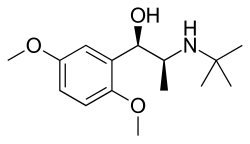

The alpha blockers mostly act in our smooth muscles, especially the ones that control the size of vessels.[3] Thus, alpha1 blockers can dilate blood vessels and decrease the blood pressure.[3] Depending on its site of action, it can be used to treat different diseases.[3] They can be used to treat signs and symptoms of benign prostatic hyperplasia, hypertension (but not as first line agent), pheochromocytoma, extravasation management and reversal of local anesthesia.[3]

There are some off- label use as well, such as chronic prostatitis and lower urinary tract symptoms in males, ureteral calculus expulsion, ureteral stent-related urinary symptoms.[3] It can be used in post-traumatic stress disorder, Raynaud phenomenon, hypertensive crisis, extravasation of sympathomimetic vasopressors, problem with urine related to neurogenic bladder, functional outlet obstruction and partial prostate obstruction.[3]